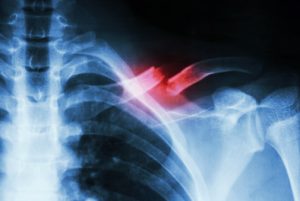

Initially, when first seeing a doctor or medical professional for a potentially broken collarbone (clavicle fracture), they will first examine it and determine how it occurred. Then the most likely next course of action will be to get some images, most likely X-rays, of the clavicular bone and surrounding bones and joints to rule out any collateral damage. The doctor will likely next prescribe a form of treatment they feel is suitable for your particular situation. The following are treatments for a fractured collarbone: